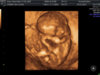

ImageUploadedByBV Forum1422262299.000662.jpg akkurat vært på ultralyd igjen, i utgangspunktet uke 9+6, men ble satt til 9+0 i dag. Så får vi se på ordinære hva terminen blir:) Så en liten en som lå og slappa av først, og så flytta den litt rolig på seg:) moro! <3 Fikk heldigvis utvendig ultralyd i dag! :D

Vårt lille nurk :Heartpink

Ble satt tilbake 5 dager, men fikk se en kropp som sprellet og et hjerte som slo. Fikk høre hjerteslag også :D